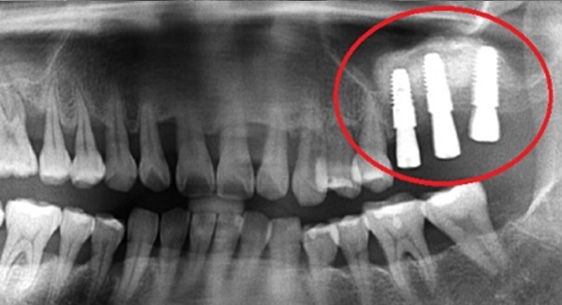

타 치과 에서 6개 치아를 발치하고 12개 임플란트 식립을 진단받고 내원. 고운미소에서 레이저 치주치료로

치아를 보존 시키고 6개의 임플란트 식립한케이스